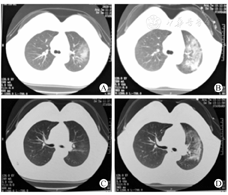

例1 女性,39岁,肾移植术后22个月。长期居住于武汉市东西湖区,2019年1月16日因发热2 d就诊,最高体温37.4 ℃,无咳嗽咳痰,尿量约2 L/d。既往史:2018年3月因"尿毒症"行肾移植术,目前口服泼尼松+吗替麦考酚酯+他克莫司三联抗排斥治疗,在本院门诊定期复诊,血肌酐约170 μmol/L;高血压10年,最高血压250/120 mmHg,目前口服厄贝沙坦150 mg/d、苯磺酸氨氯地平10 mg/d(一日2次)、倍他洛克缓释片23.75 mg/d,自述血压控制可。查体:体温37 ℃,脉搏90次/min,呼吸20次/min,血压112/69 mmHg,余无特殊。我院门诊血常规检查提示白细胞正常范围,淋巴细胞减低,他克莫司血药浓度8.3 μg/L,血肌酐182 μmol/L,胸部CT提示肺部感染(图1)。

例1 2020年1月17日最高体温38.7 ℃,后体温逐日下降,2020年1月18日最高体温37.3 ℃,2020年1月19日最高体温36.9 ℃,自感无异常,睡眠、食欲、精神均可。入院辅助检查结果:细菌、真菌、病毒等均阴性;复查血常规白细胞正常范围(4.24×109/L,参考区间3.5×109~9.5×109/L),较入院时有下降趋势;淋巴细胞计数低(0.60×109/L,参考区间1.0×109~3.2×109/L,发病前随访淋巴细胞计数均在正常值范围);CRP增高(43.4 mg/L,参考区间0~10 mg/L);PCT临界范围(0.101 μg/L,参考区间<0.1 μg/L);细胞免疫提示机体免疫力极低(CD4计数186×109/μL,参考区间404×109~1 612×109/μL)。受者体温逐渐恢复正常,未调整治疗方案。2020年1月20日再次出现发热,最高体温38.3 ℃,少许干咳,尿量约2 L/d,查体无明显阳性体征,辅助检查结果:他克莫司血药浓度7.6 μg/L、血肌酐197 μmol/L,排斥反应可能性小。立即复查胸部CT对比2020年1月16日CT提示:双肺感染,较前进展(图1)。拟行纤维支气管镜检查,受者拒绝。调整治疗方案:停服他克莫司,改为甲泼尼龙40 mg/d静脉滴注,给予人血丙种球蛋白10 g/d静脉滴注,口服头孢哌酮钠他唑巴坦钠改为盐酸莫西沙星继续联合磺胺抗感染,继续更昔洛韦+奥司他韦抗病毒,继续泊沙康唑抗真菌治疗,申请2019-nCoV核酸检测,同时给予单间病房隔离治疗。

肾移植受者长期使用免疫制剂在有效降低机体排斥反应的同时也极大程度的减低了机体对病毒、细菌等病原体感染的免疫能力,肺部感染是肾移植术后主要的感染类型之一,具有起病隐匿、进展快、病情严重等特点[5,6]。本研究2例肾移植受者于2020年1月14日出现COVID-19的初期症状均是发热(中低热),无咳嗽咳痰,饮食、睡眠、精神均可,受者自我舒适度可,胸部CT为双肺多发的斑片状、片状磨玻璃阴影。2020年1月20日均症状加重,CT提示双肺感染进展,新发病灶主要以双肺中下叶为主。其中例1快速出现低氧血症,CT出现大片状毛玻璃影。例2的临床表现、CT改变与报道的COVID-19发病过程及影像学改变高度相似:以发热为起病表现,1周后出现呼吸困难和/或低氧血症,病情进展后两肺多发磨玻璃影。